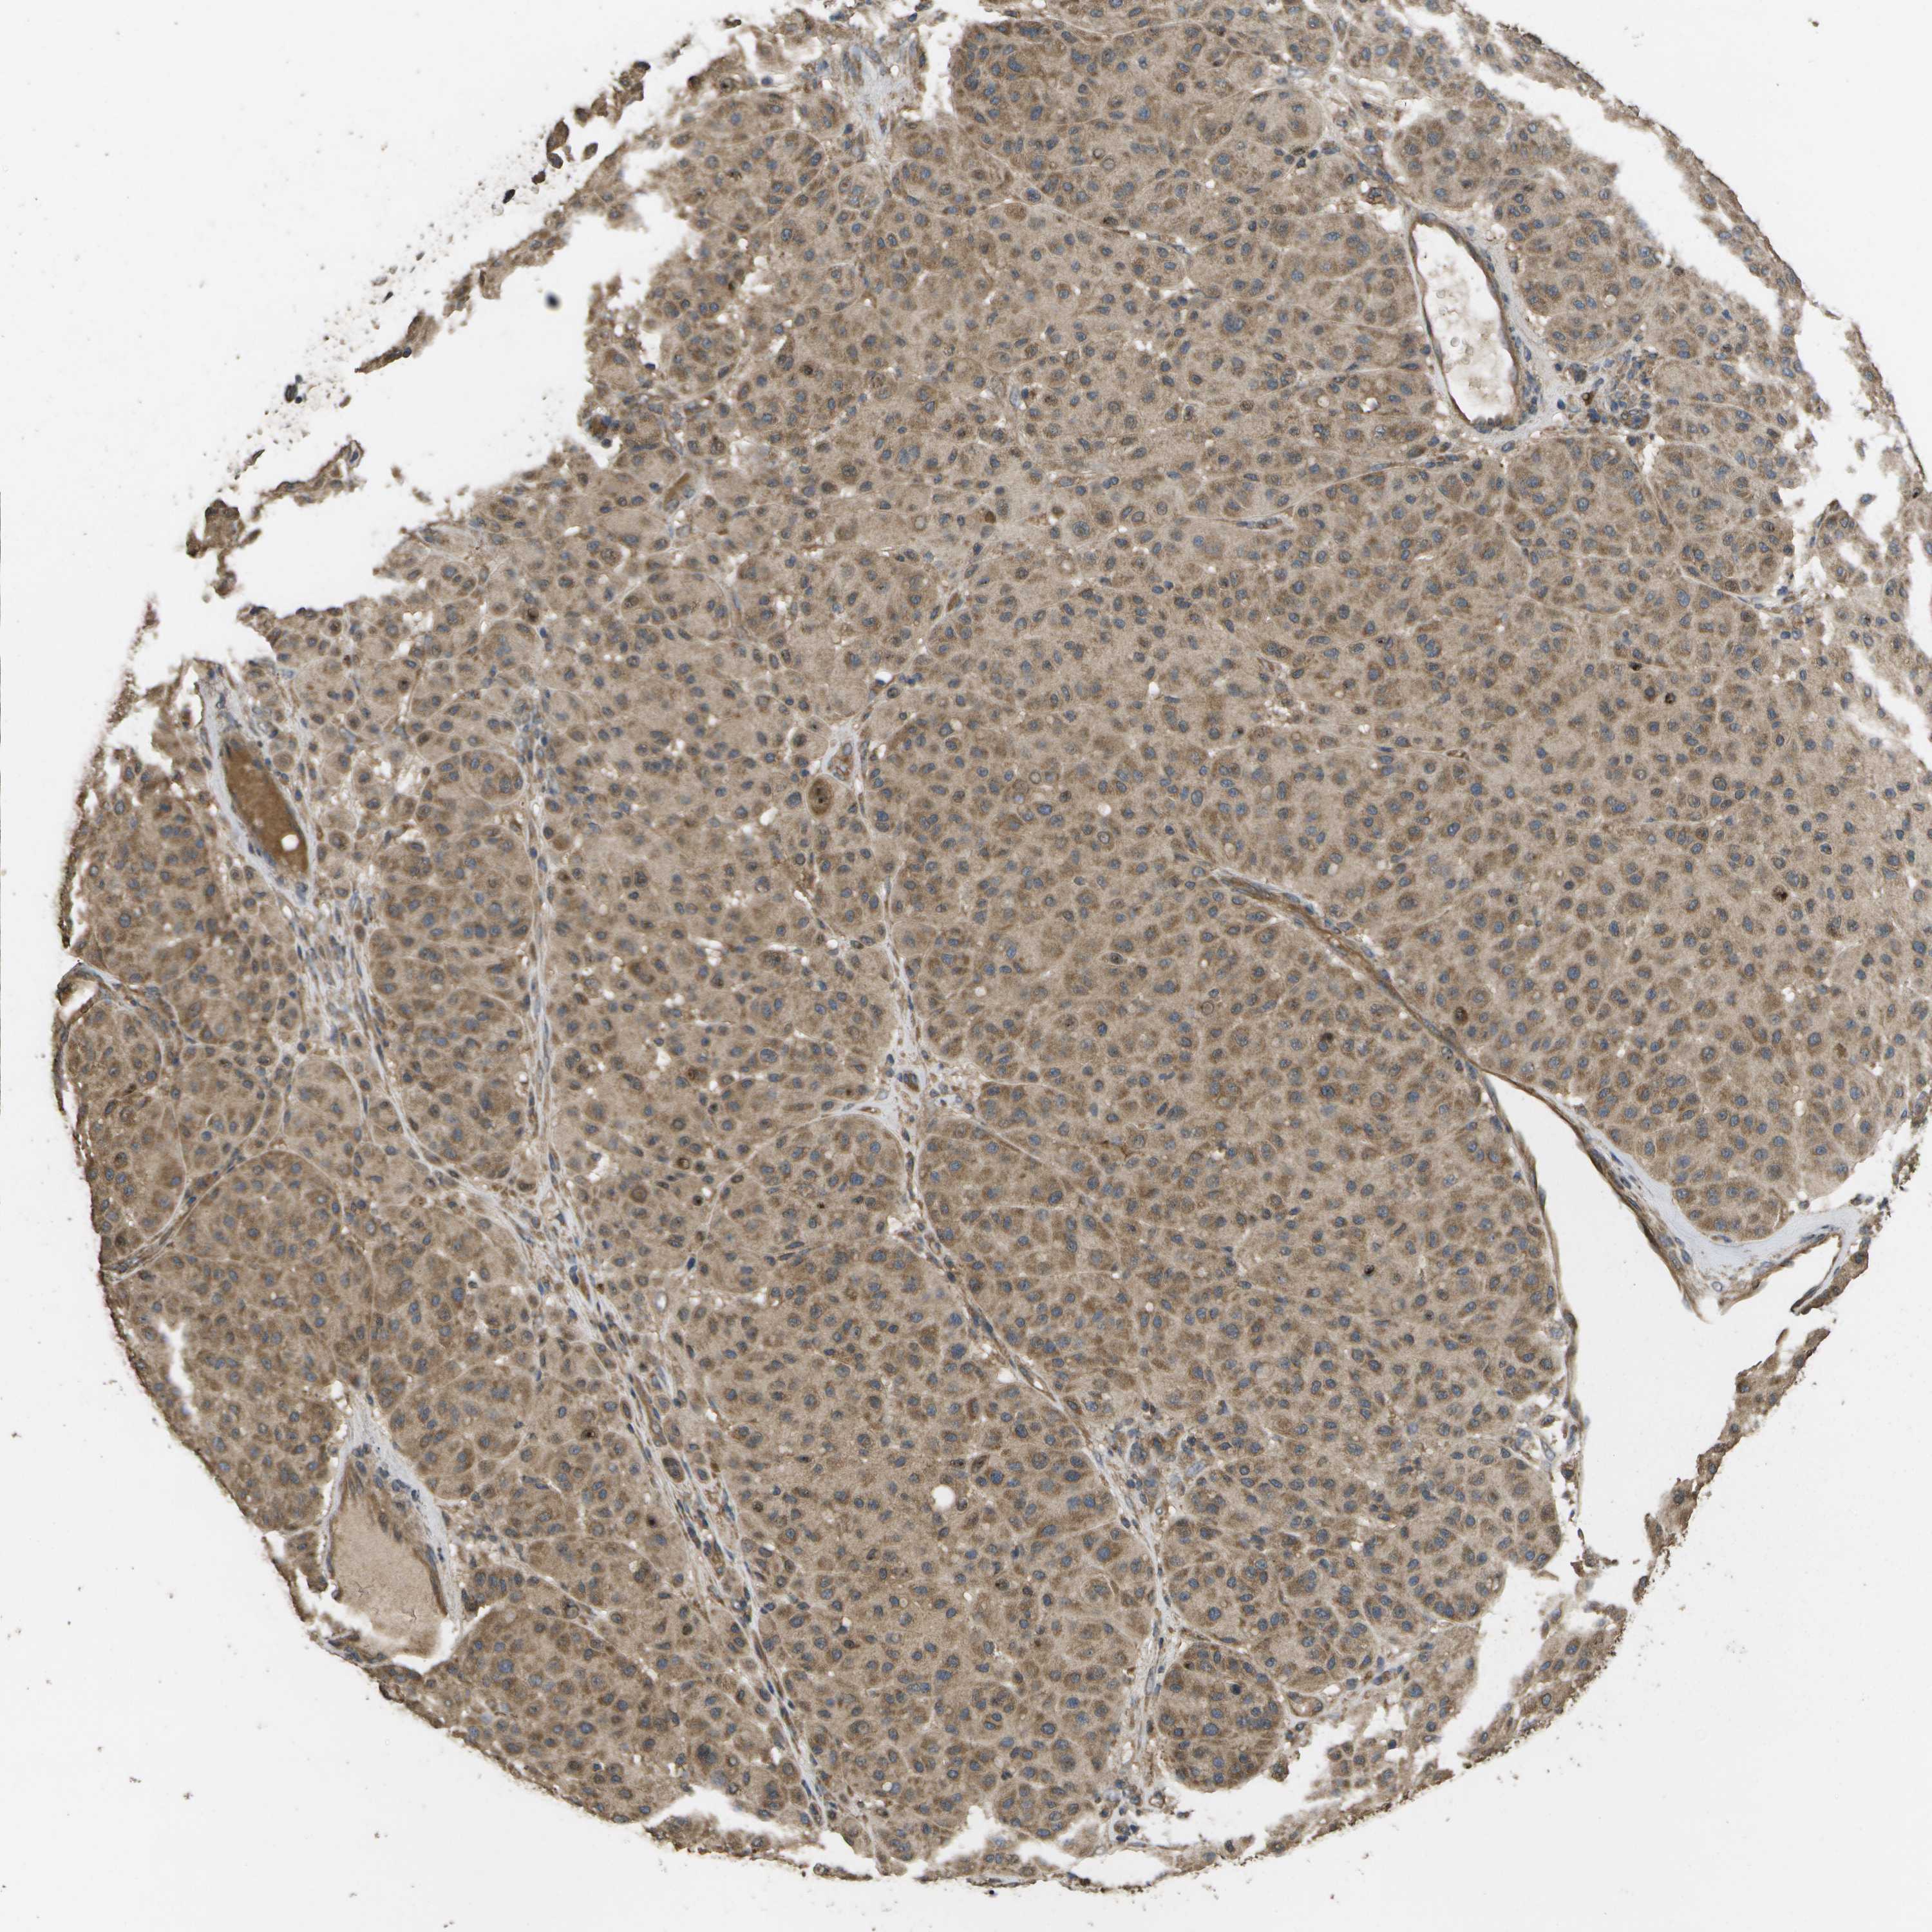

MELANOMA - Protein expressioni

A mouse-over function shows sample information and annotation data. Click on an image to view it in a full screen mode. Samples can be filtered based on level of antibody staining by selecting one or several of the following categories: high, medium, low and not detected. The assay and annotation is described here.

Note that samples used for immunohistochemistry by the Human Protein Atlas do not correspond to samples in the TCGA dataset.

Antibody stainingi

Antibody staining in the annotated cell types in the current human tissue is reported as not detected, low, medium, or high, based on conventional immunohistochemistry profiling in selected tissues. This score is based on the combination of the staining intensity and fraction of stained cells.

Each image is clickable and will lead to virtual microscopy that enables deeper exploration of all samples and also displays staining intensity scores, fraction scores and subcellular localization as well as patient and tissue information for each sample.

Antibody CAB017714

Staining

High

Medium

Low

Not detected

Intensity

Strong

Moderate

Weak

Negative

Quantity

>75%

75%-25%

<25%

None

Location

Nuclear

Cytoplasmic/membranous

Cytoplasmic/membranous,nuclear

Malignant melanoma, NOS

Malignant melanoma, Metastatic site